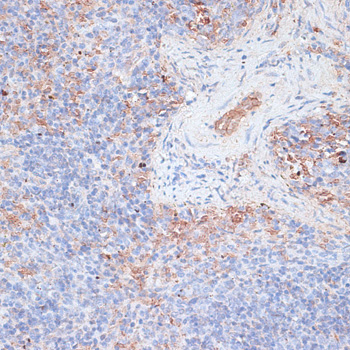

Immunohistochemistry of paraffin-embedded human appendix using CTSG at dilution of 1:100 (40x lens).

Immunohistochemistry of paraffin-embedded human uterine cancer using CTSG at dilution of 1:100 (40x lens).

Immunohistochemistry of paraffin-embedded mouse spleen using CTSG at dilution of 1:100 (40x lens).